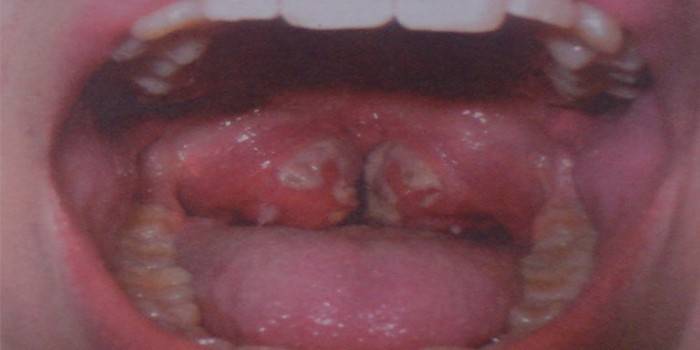

Amigdalite

Candida tonsilite é mais adequado para o termo "amigdalite fúngica", uma vez que com ele o processo inflamatório afeta apenas as amígdalas. Caso contrário, esse tipo de amigdalite é chamado amigdalose. A doença se manifesta com dor leve ao engolir, sensação de formigamento na garganta e tosse seca. Tudo isso é acompanhado por fraqueza geral, mal-estar e um leve aumento na temperatura corporal.

- Tamanho, área de distribuição e tipo de placa branca. Com uma forma fúngica, tem uma aparência coagulada, e com uma forma bacteriana é representada por abscessos. No primeiro caso, a placa é localizada na língua, palato e amígdalas, e no segundo - apenas nas amígdalas. Após a sua remoção, com amigdalite fúngica, as feridas com sangramento permanecem, e com a mucosa bacteriana, ele simplesmente fica vermelho.

O principal sintoma da doença é a placa, que pode cobrir não apenas as amígdalas, mas também toda a superfície da faringe, amígdalas e parede posterior. Tem uma tonalidade esbranquiçada se a candidíase for o agente causador e esverdeada se for mofada. Outros sintomas característicos de tonsilomicose:

- coalhada branca solta nas amídalas.